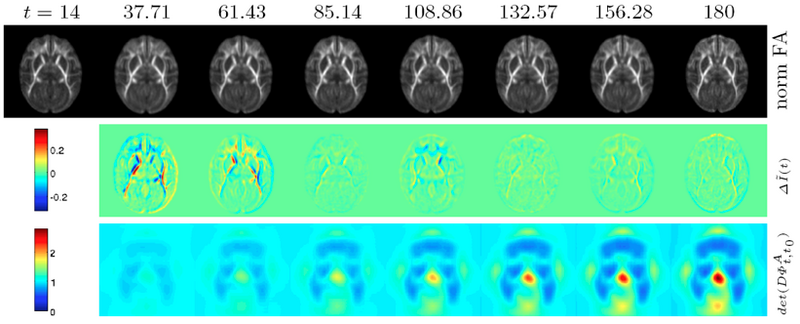

Longitudinal macaque developmental DTI atlas from postnatal day 14 to 180 as visualized on a center axial slice. Top row: Reconstructed atlas image at each age pulled back to day 14. The high quality of the longitudinal modeling is visible through the close similarity of the pulled-back atlas images. Middle row: Estimated change in FA between time points displaying major change occurring in the first 60 days (overshadowing the magnitude of later changes). Bottom row: Jacobian determinant of the pull-back deformation field. Cyan = no change, dark blue = growth (most of white matter), yellow-red = shrinkage (here seen on the 3rd ventricle in the center of the image)